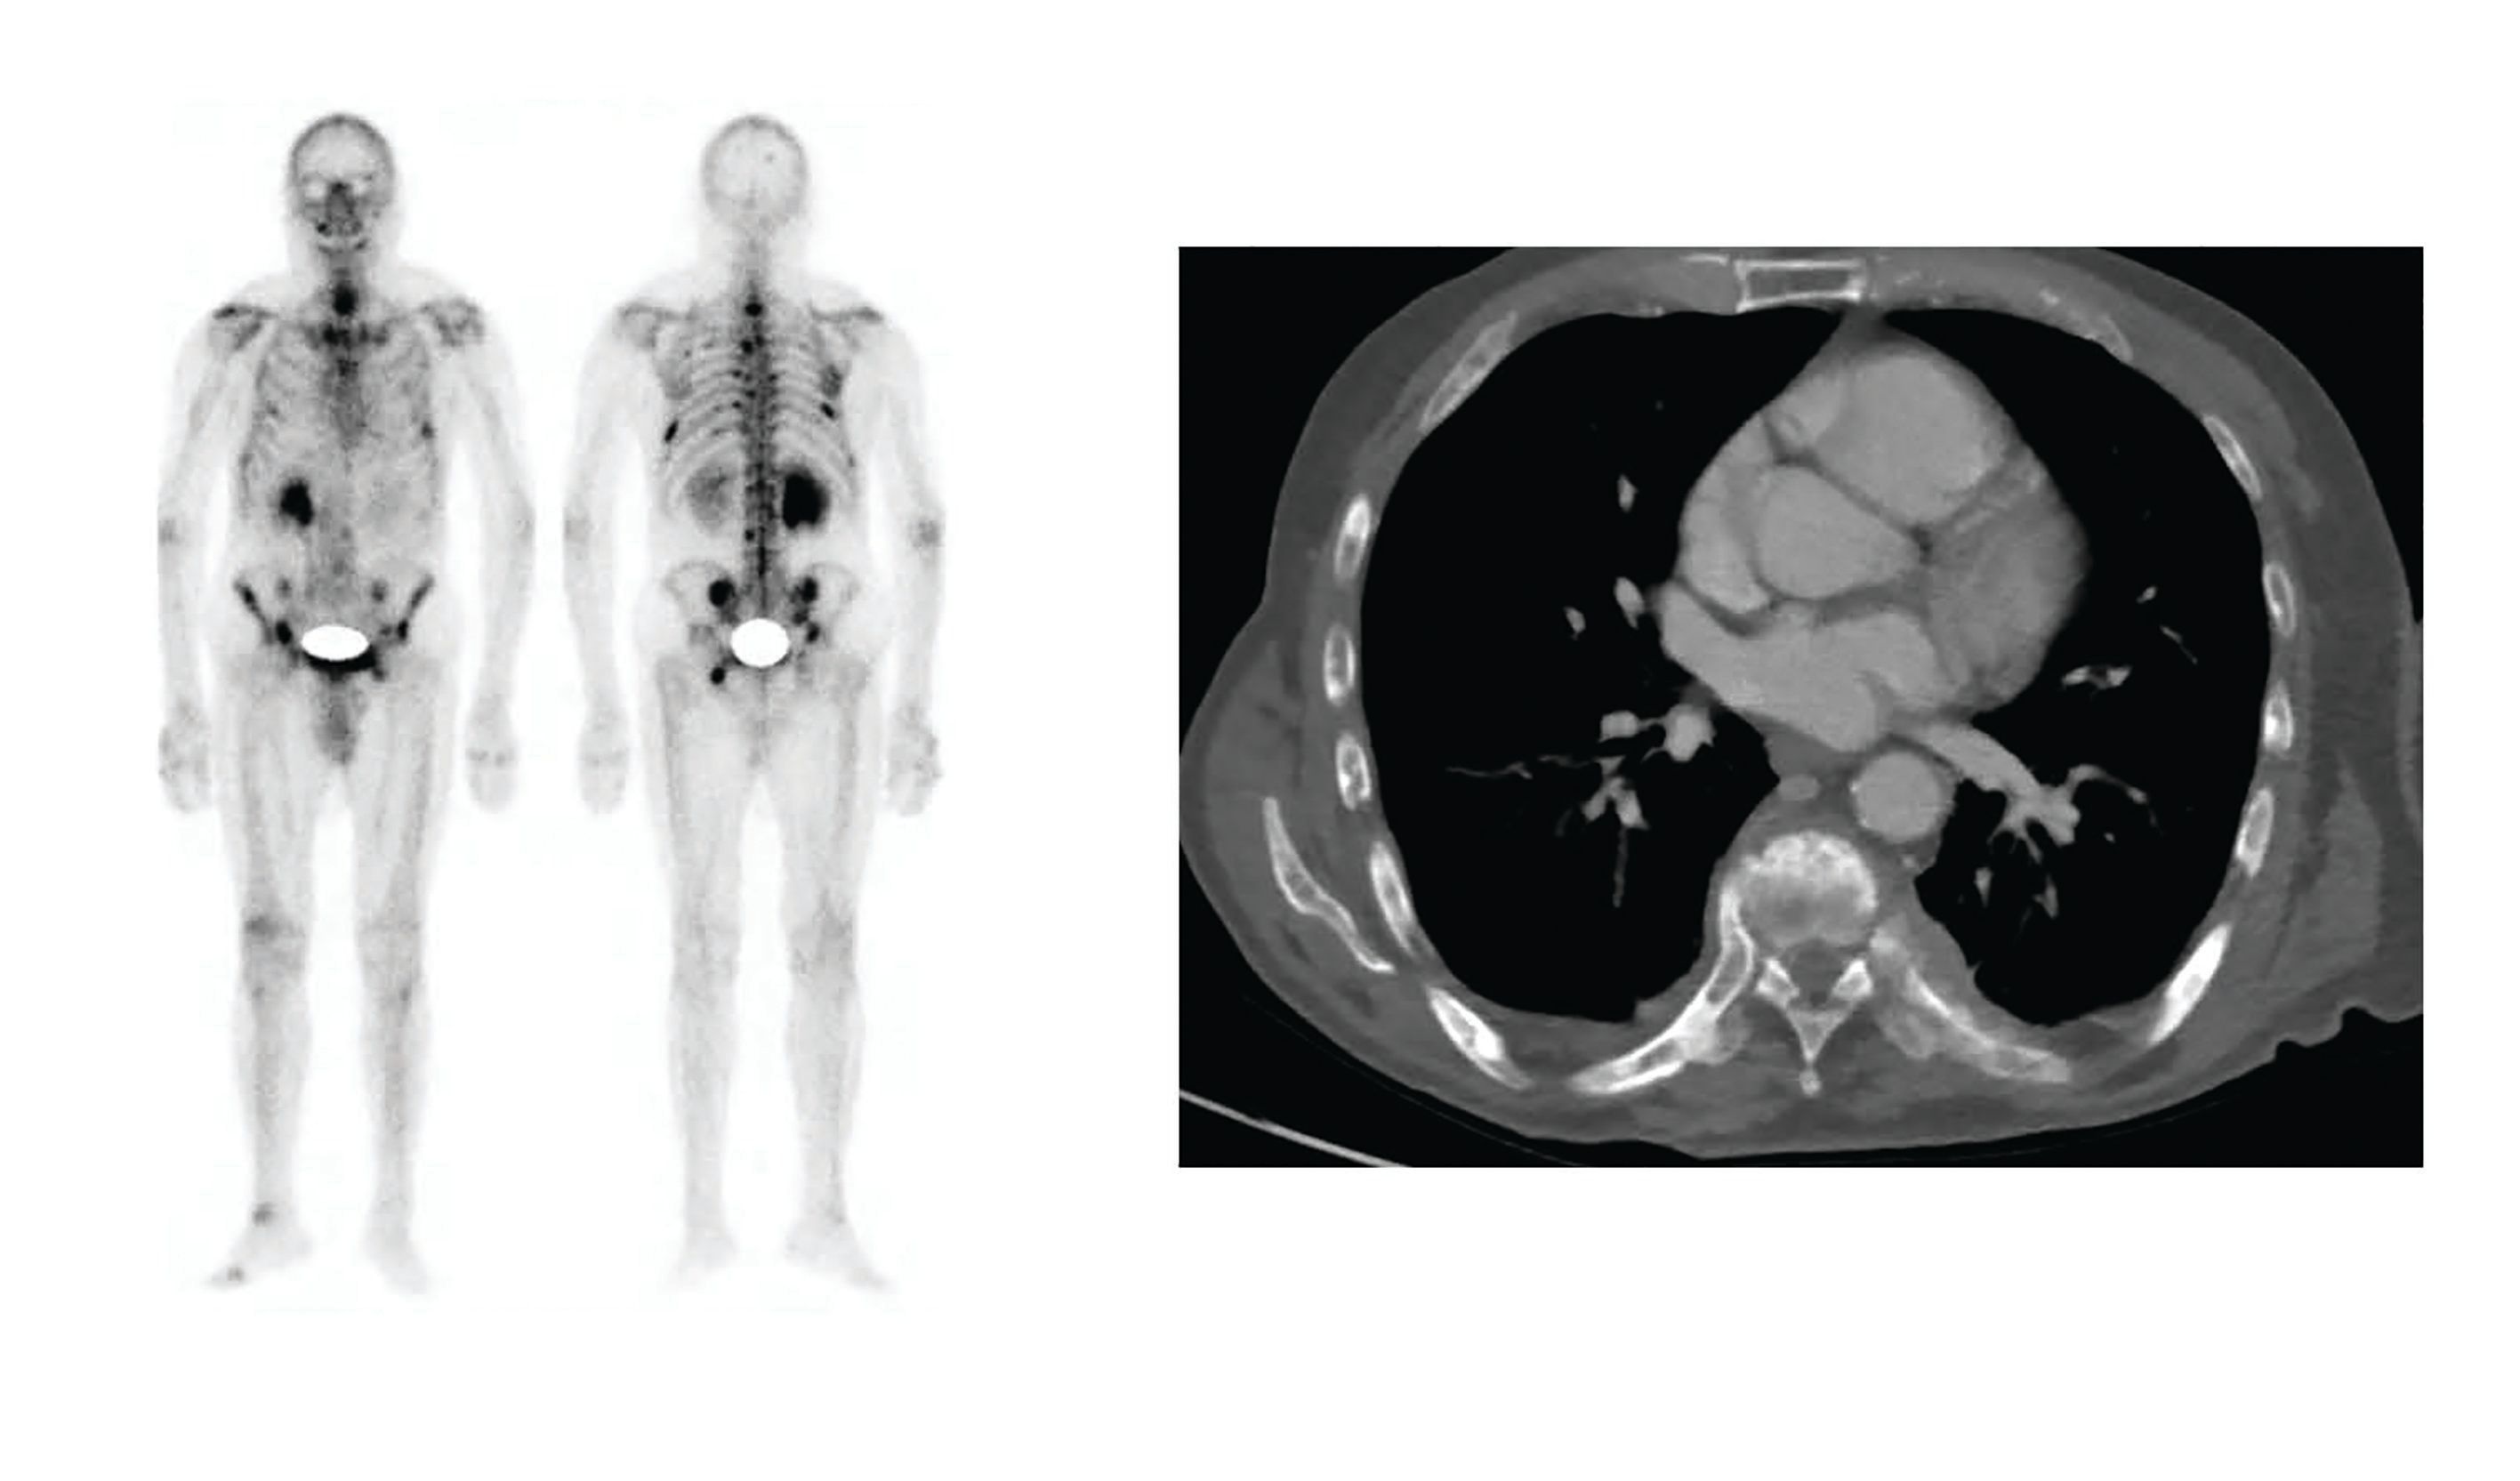

Figure 1. A bone scan showed metastases in both iliac crests, the ischium, cervical spine, and ribs (left). A computed tomography scan showed bilateral subpleural nodules consistent with metastatic disease (right).

Six months later, disease progression was documented with a PSA level of 262 ng/mL, an increase in number of bone lesions, and new metastatic bilateral subpleural nodules (Figure 1).